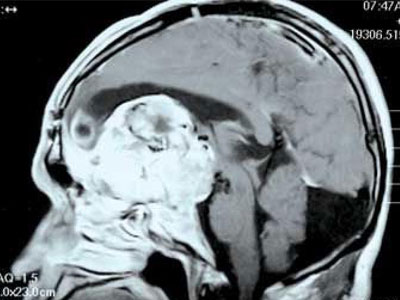

17世纪的法国哲学家有一句名言:“我思故我在”。可以看出,意识在很长时间里都是哲学讨论的话题。现代科学认为,意识是从大脑中数以亿计的神经元的协作中涌现出来的。但是这仍然太笼统了,具体来说,神经元是如何产生意识的?近年来,科学家已经找到了一些可以对这个最主观和最个人的事物进行客观研究的方法和工具,并且借助大脑损伤的病人,科学家得以一窥意识的奥秘。除了要弄清意识的具体运作方式,科学家还想知道一个更深层次问题的答案:它为什么存在,它是如何起源的?

美好的记忆、悲伤的记忆,关于解方程技巧的记忆,英语单词的记忆,毫无疑问它们都储存在我们的大脑中。但是它们具体在什么部位?

上个世纪50年代,科学家发现大脑中的“海马区”在存储信息的过程中扮演着至关重要的角色——如果切除掉海马区,那么以前的记忆就会一同消失。但是海马区的神经细胞如何把信息固定下来?科学家发现一些分子参与到了记忆的形成。此外,神经细胞突触地形成也与记忆相关联。但是,科学家目前对于记忆的运作机制的了解还不够——而这一机制对于理解我们自身是非常重要的。